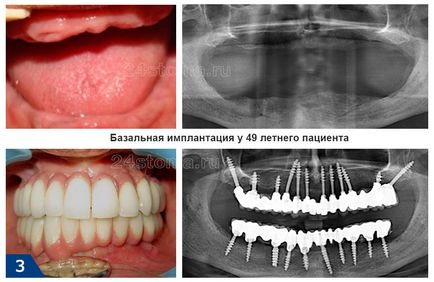

Basal имплантиране - е метод, който включва монтирането на зъбни импланти в базалния слой на челюстта костна тъкан, която се характеризира със специална плътност и не подлежи на атрофия (резорбция). Този метод се нарича имплантация на една сцена, т.е. можете да получите вашите зъби само за един ден, без присаждане на кости.

Имплантирането без присаждане на кост (дори и в случай на значителна липса на костния обем) и такъв ранен протеза са възможно благодарение на специалния дизайн на имплантите и тяхното фиксиране в гъста базалната кост. Всички тези базалната имплантация е коренно различна от техниката на класическия имплантация.

Фото базални импланти -